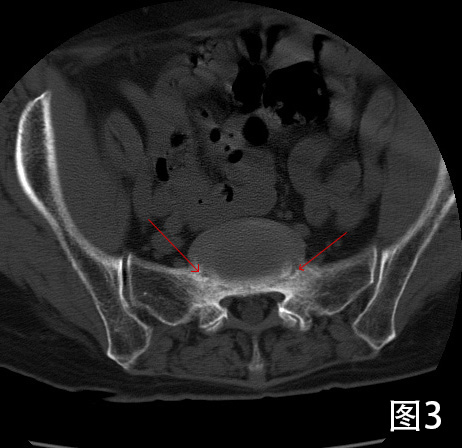

专科检查:2022-08-17 腰椎CT平扫检查阅片:腰椎椎体序列不稳定,椎管内可见增生钙化,继发椎管骨性狭窄。根据Meyerding分级, L4椎体向前I度滑脱,L5椎体向前II度滑脱,为连续2个节段的退行性滑脱(图1)。L3/4、L4/5、L5/S1椎间盘膨出,硬膜囊受压。L4、L5椎体小关节增生硬化明显,相应节段竖脊肌萎缩。椎间盘于相邻椎体层面以相反方向超出椎体边缘“夹心征”(图2)。L5椎体假关节形成(图3)。